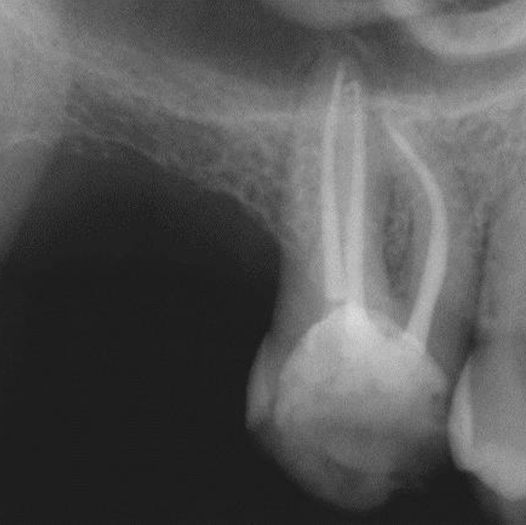

Before

After

Before Root Canal treatment

After Root Canal treatment